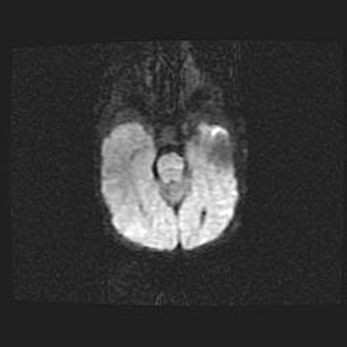

Церебральная ишемия II.

Возраст: 7 дней

Вес: 3350 г

Пол: женский

Окружность головы: 35 см

Срок гестации: 39 недель

Ишемия головного мозга – это состояние, которое развивается в ответ на кислородное голодание вследствие недостаточного мозгового кровообращения. У новорожденных она является следствием дефицита кислорода, что ведет к метаболическим расстройствам различной степени тяжести в тканях головного мозга, в том числе к развитию коагуляционных некрозов и гибели нейронов.